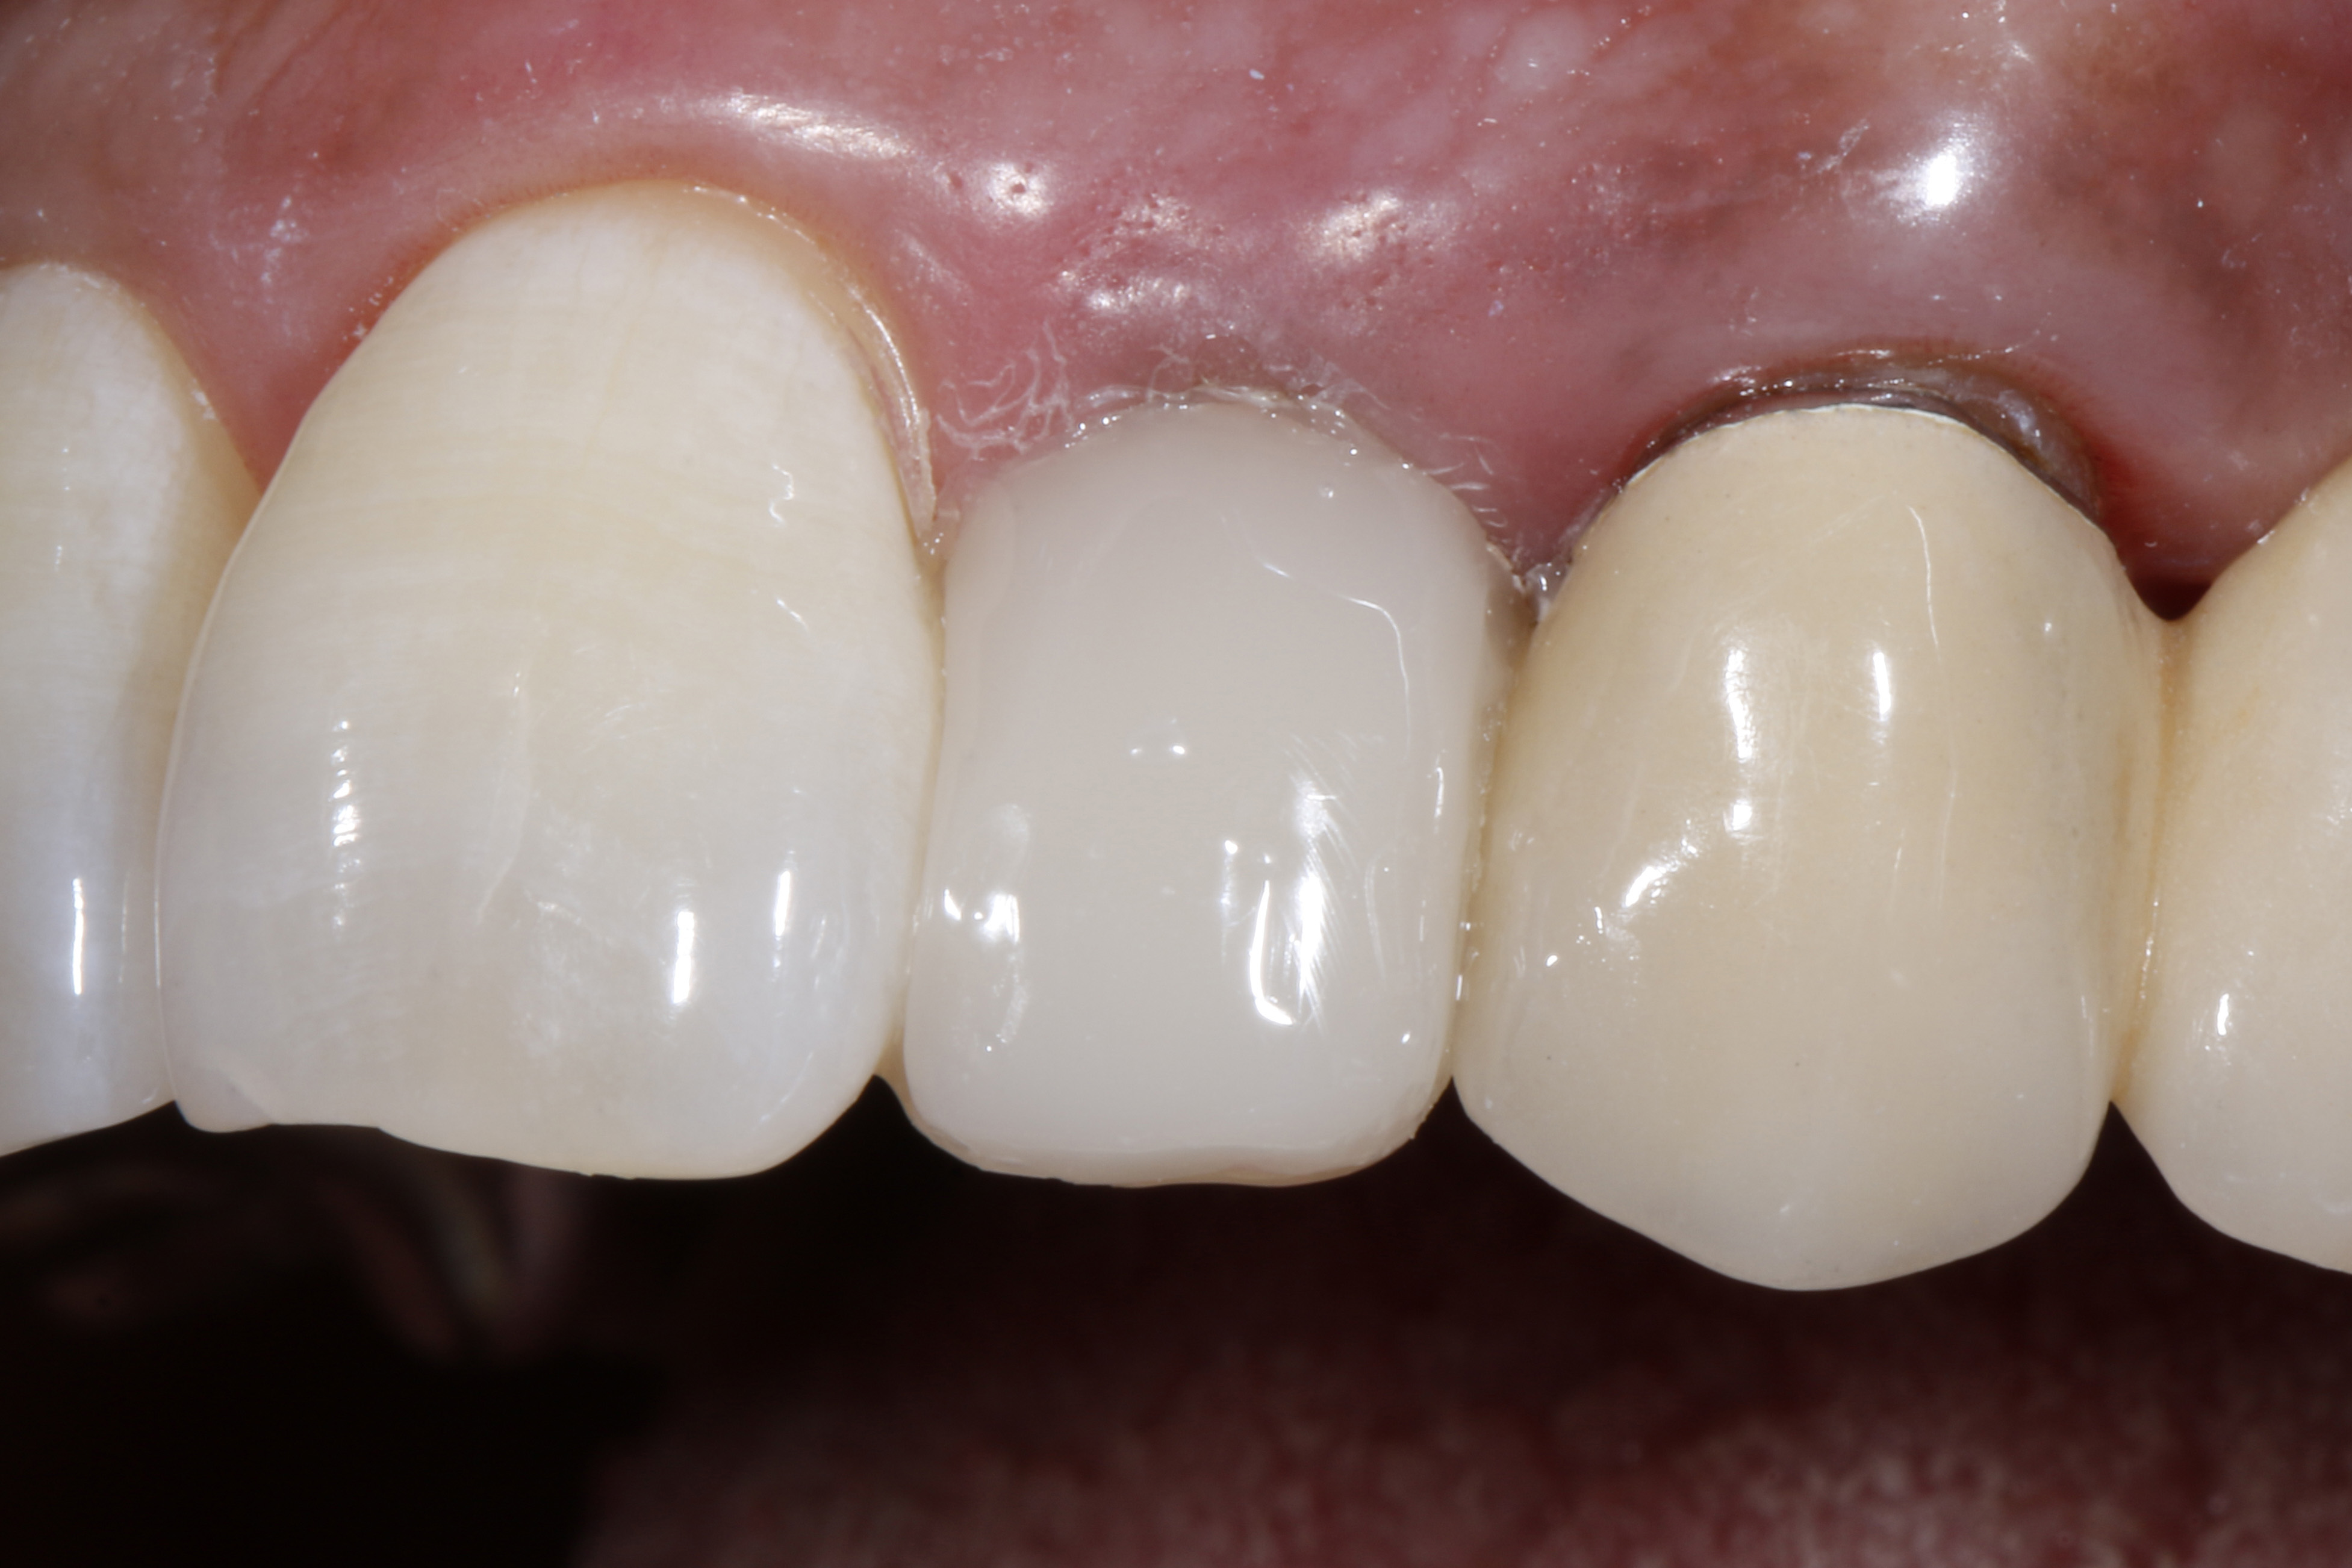

Do naszego gabinetu stomatologicznego zgłosiła się 60-letnia pacjentka z prośbą o lepsze optyczne ustawienie w łuku zębowym lewego bocznego siekacza szczęki, który jest wyraźnie położony podniebiennie w stosunku do lewego siekacza centralnego (ryc. 1 i 2).

Oprócz samego zęba, pacjentce szczególnie przeszkadzał fakt, że ząb wydawał się znacznie ciemniejszy w uśmiechu w porównaniu z lewym siekaczem centralnym i koroną PFM na lewym kle. Ząb bezzwłocznie zareagował nadwrażliwością na test na zimno, nie wykazał przy tym nieprawidłowości w teście opukiwania. Po zapoznaniu się z możliwymi alternatywami leczenia i ich kosztami, pacjentka zdecydowała się na licówkę bezpośrednią z użyciem uniwersalnego kompozytu GrandioSO Unlimited (VOCO GmbH, Cuxhaven).

Ryc. 1, 2. Sytuacja wyjściowa: lewy siekacz boczny jest ustawiony wyraźnie podniebiennie w stosunku do zębów sąsiednich. To przeszkadza pacjentce, który chciałaby uzyskać lepszą integrację wizualną z łukiem zębowym.